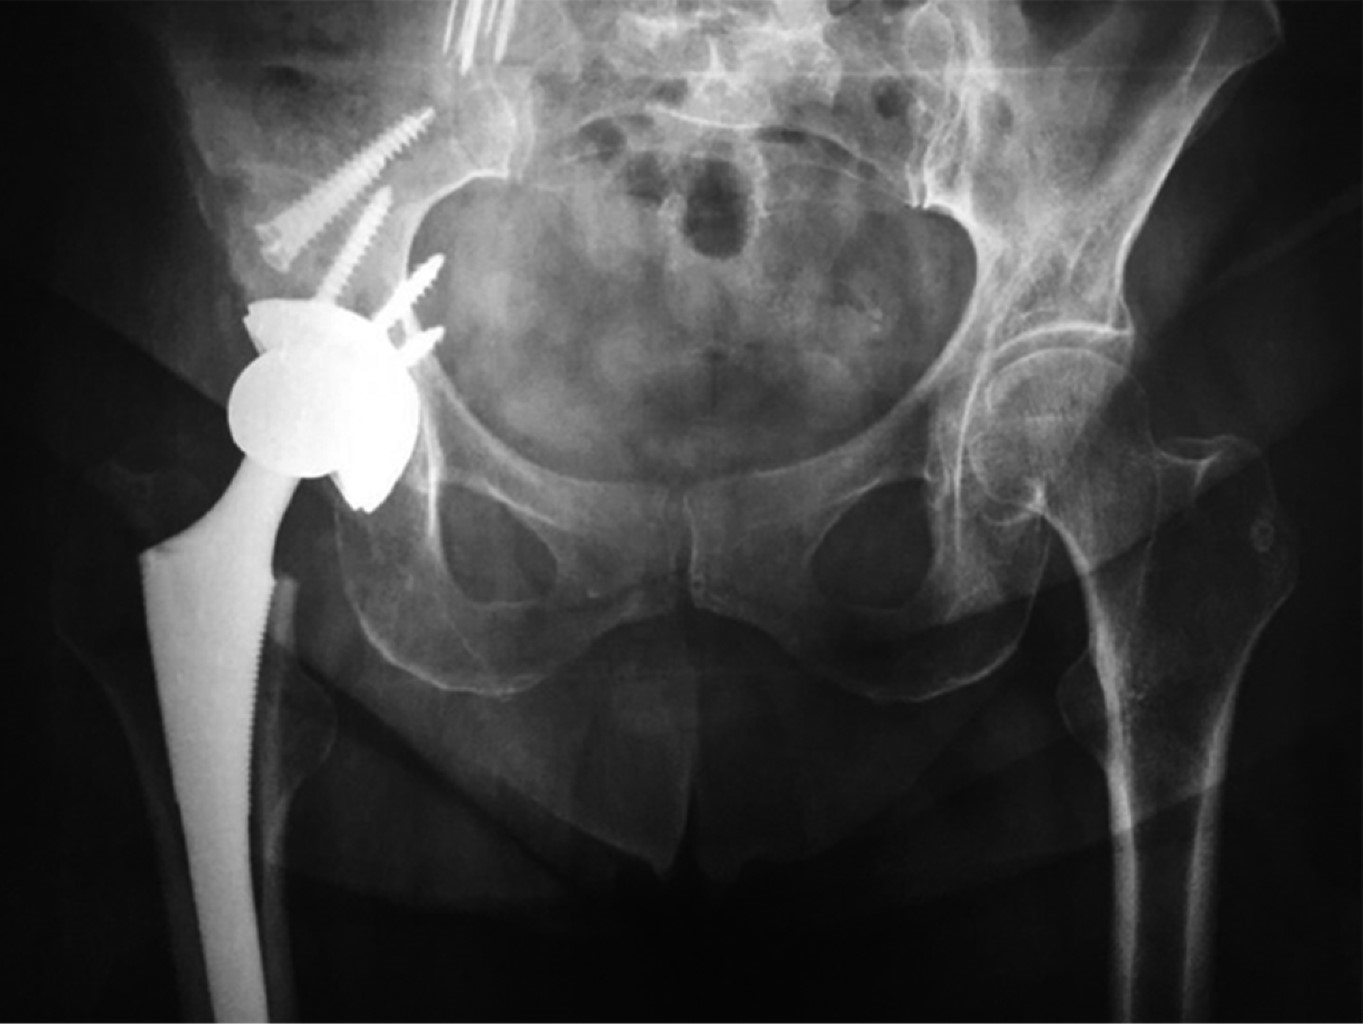

Paciente femenino de 71 años que se somete a artroplastía primaria total de cadera derecha secundaria a coxartrosis, con un resultado quirúrgico no satisfactorio en radiografía de control al finalizar la colocación de los componentes debido a una mala orientación del componente acetabular (Figuras 1 y 2), dejando una zona de pérdida en el techo acetabular original. Se decide en ese momento la conservación de la cabeza femoral en tejidos blandos para colocar como injerto en segundo tiempo quirúrgico (Figura 3), el cual se realizó dos semanas posteriores al primer procedimiento, reconstruyendo defecto con injerto de cabeza y fijándolo con tornillos acetabulares 6.5 mm. El componente acetabular constó de una copa Refletion (Smith & Nephew, Memphis, TN, USA) de recubrimiento poroso fijada con tres tornillos acetabulares 6.5 mm y vástago no cementado Synergy (Smith & Nephew, Memphis, TN, USA).

Figura 2